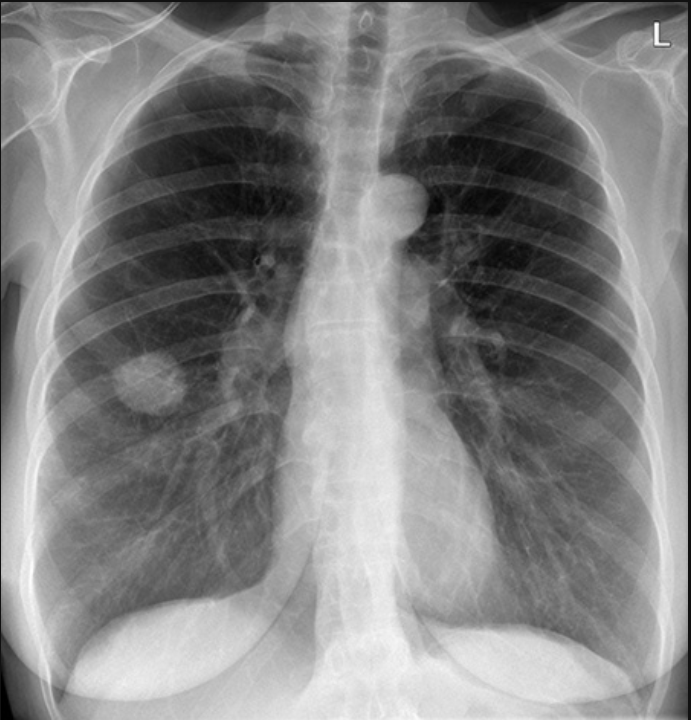

Chest X-Ray Abnormal Detection

Self-supervised anomaly detection for chest radiographs

1.png